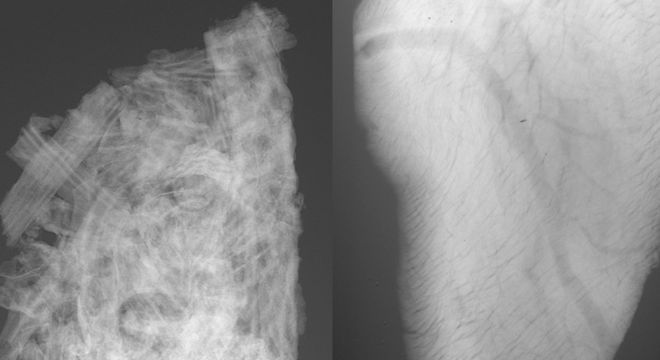

À esq., raio-x de uma rocha carbonática, mesma composição encontrada nos reservatórios do pré-sal; e à dir., raio-x de um corte do ventrículo esquerdo de um coração de camundongo

O Sirius, a maior construção científica já feita no Brasil, estimada em R$ 1,8 bilhão, revelou suas primeiras imagens nesta quinta-feira (19). Trata-se de dois raios-x, um tirado de uma rocha e outro do coração de um camundongo.

"Estamos trabalhando em condições de testes e, mesmo assim, os raios X de alta energia produzidos pelo Sirius impressionam. Além de aumentarmos a qualidade da imagem, vamos conseguir analisar amostras de maior tamanho. Esse é um ponto importante, quando planejamos investigar rochas do pré-sal, por exemplo", afirmou.

As primeiras imagens, feitas em uma estação experimental, têm a finalidade de avaliar uma série de sistemas do Sirius. Elas vão guiar os ajustes necessários para que a luz síncrotron atinja a qualidade exigida, e assim sejam feitos experimentos científicos de altíssimo nível, muitos deles inéditos no mundo.